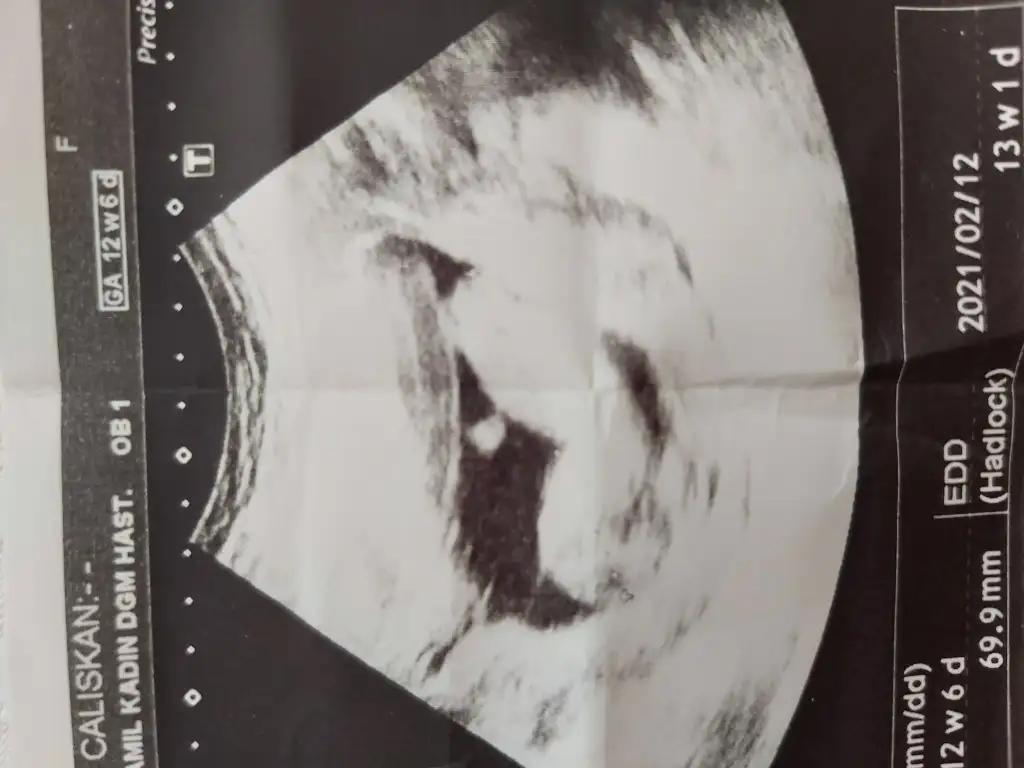

13-14 hafta arasıydı tam tarih bilmiyorum cnmEvet pipi var gibikaç haftalık USG cnm 11 12 13 haftalar olmalı

Yani erkek gibi geldi bana cnm13-14 hafta arasıydı tam tarih bilmiyorum cnm

Net değil USG sanki sanki dersem erkek ama emin olamadım başka USG paylaşınBizede cinsiyet tahmininde bulunur musunuz?